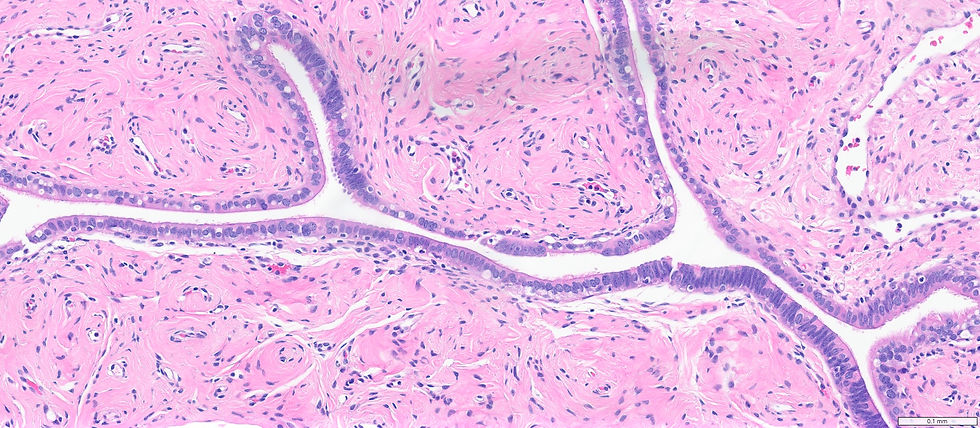

A 70-year-old female presented with a 8.0 cm ovarian mass. Frozen section was done and a malignant process can not be ruled out. Here is the BSO-TAH specimen.

The fallopian tube section in this patient showed:

Benign unremarkable tube but the right corner starting to look like bluer (high N:C ratio) 3. What's the interpretation of the fallopian tube finding?

The findings are suggestive for serous tubal intraepithelial carcinoma (STIC) and serous carcinoma in figure 1. The morphology features for STIC include a high N:C ratio, nuclear enlargement, pleomorphism, hyperchromasia, loss of ciliated cells, loss of polarity, epithelial stratification, and occasionally mitotic figures. STIC needs to be confirmed by abrrent p53 and >10% Ki-67. In figure 1 the tumor invades into fallopian stroma making it serous carcinoma.